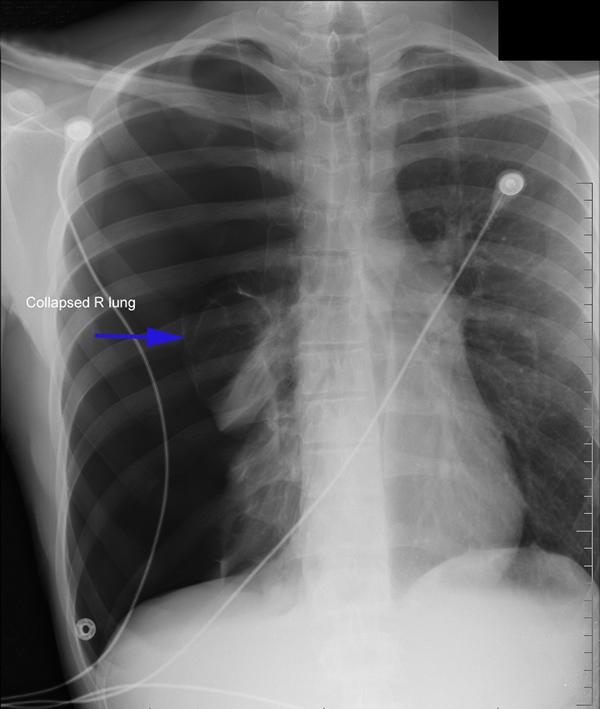

Patients who have had a second episode of spontaneous pneumothorax are those most likely to be considered for thoracoscopic pleurectomy and apical blebectomy. However, patients with a first episode of spontaneous pneumothorax who have a prolonged air leak (greater than 72 hours), incomplete expansion of the lung (Figure 1), bilateral pneumothoraces, associated hemothorax, tension pneumothorax (Figure 2), or a bleb on their CT scan (Figure 3) should be offered surgery at the time of the first occurrence [1]. Patients who have had a spontaneous pneumothorax and whose occupation places them at risk for a second episode or places them in a situation where medical intervention is not readily accessible should be considered for surgery. Therefore divers, pilots, submarine personnel, and those that work or live in the wilderness or space are suitable patients [1].

| Figure 1: Chest x-ray showing incomplete expansion of lung after chest tube placement. | Figure 2: Chest x-ray showing tension pneumothorax with mediastinal shift. | Figure 3: CT Scan showing apical bleb. |